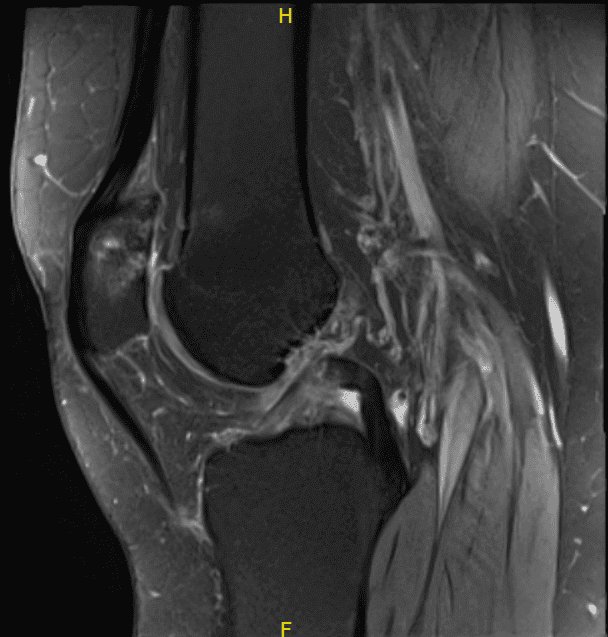

El paciente presentó resultados de resonancia magnética que mostraron condromalacia del compartimento patelofemoral moderada a marcadamente avanzada. Deshilachamiento libre del menisco medial con un colgajo horizontal orientado oblicuamente por debajo del menisco medial y condromalacia compartimental medial generalizada de leve a moderada.

Deshilachado leve del borde libre del menisco lateral sin un desgarro discreto. Derrame articular traza con un cuerpo suelto ossificado de 8 mm en la parte posterior de la articulación.

MRI-3T Rodilla izquierda sin contraste